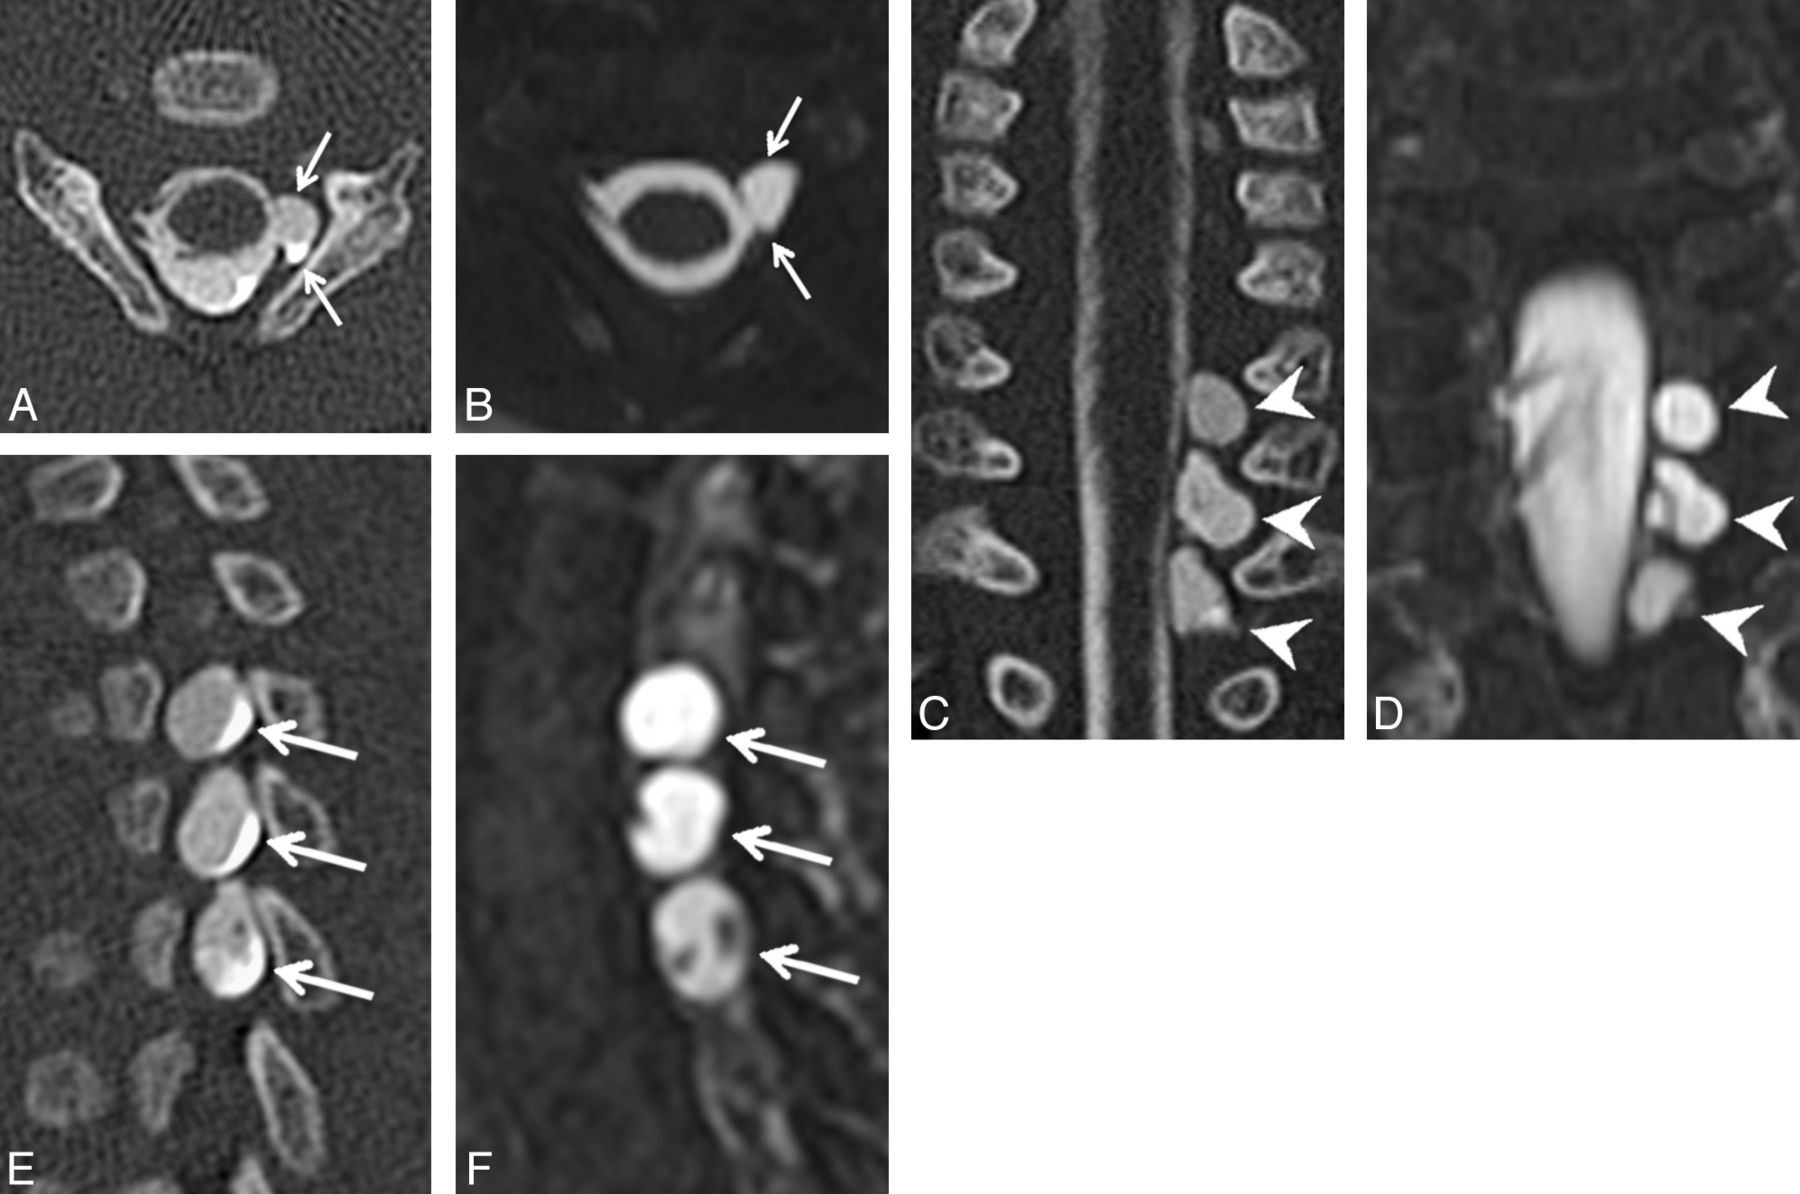

Axial (A), coronal (C), and left parasagittal (E) images from a CT myelogram and corresponding axial (B), coronal (D), and left parasagittal (F) images from an MR myelogram (B, D, and F) on the same patient demonstrating 3 consecutive left-sided pseudomeningoceles with absent rootlets at C7–T1 (arrows in A and B, arrowheads in C and D, arrows in E and F). Note the internal septa within the middle and lower pseudomeningoceles that can simulate intact rootlets on a single image.